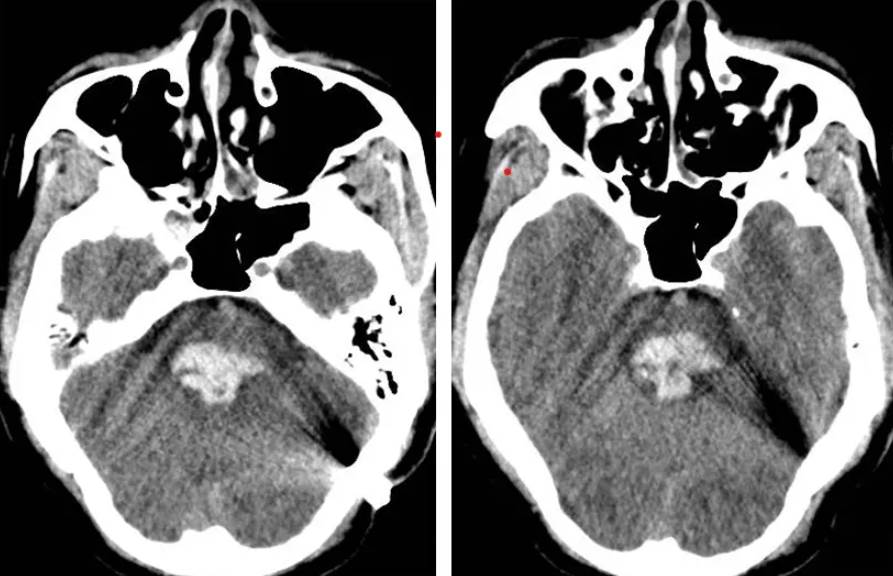

腦幹到底是什麼?為什麼一出血就這麼致命?神經外科醫師解釋,腦幹就像人體的「總電源開關」,心跳、呼吸、血壓全由它掌控。一旦出血壓迫,幾分鐘內就會致命,連搶救的時間都沒有。

更可怕的是,腦幹出血前期癥狀不明顯,很容易被忽略。醫師警告,如果出現「劇烈頭痛」(像被雷打到一樣)、莫名暈眩、走路不穩、臉麻口齒不清、視力突然模糊」,千萬別當作小事,這可能是腦幹出血的前兆!